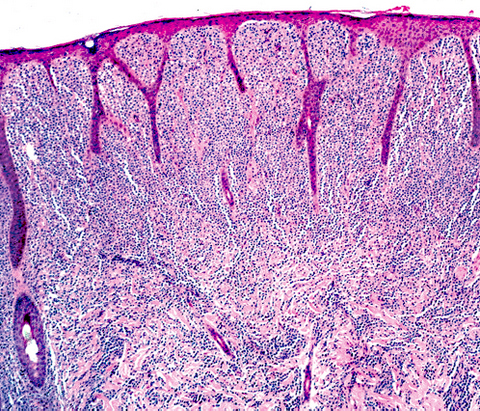

Microscopic (histologic) description

- Within the macules and plaque, mast cells are predominantly in papillary dermis

- Mast cells are round or spindle shaped with abundant eosinophilic cytoplasm, distinct cytoplasmic boundaries, large pale nuclei

- Eosinophils are often present

- Also edema of papillary dermis, subepidermal vesiculation

- Bullous mastocytosis may be diagnosed by Tzank smear; infiltrate may be slight and perivascular

- In telangiectasia macularis eruptive perstans, features may be subtle, with increased mast cells around dilated superficial capillaries, basal cell hyperpigmentation of overlying epidermis, superficial lymphohistiocytic infiltrate

Microscopic (histologic) images